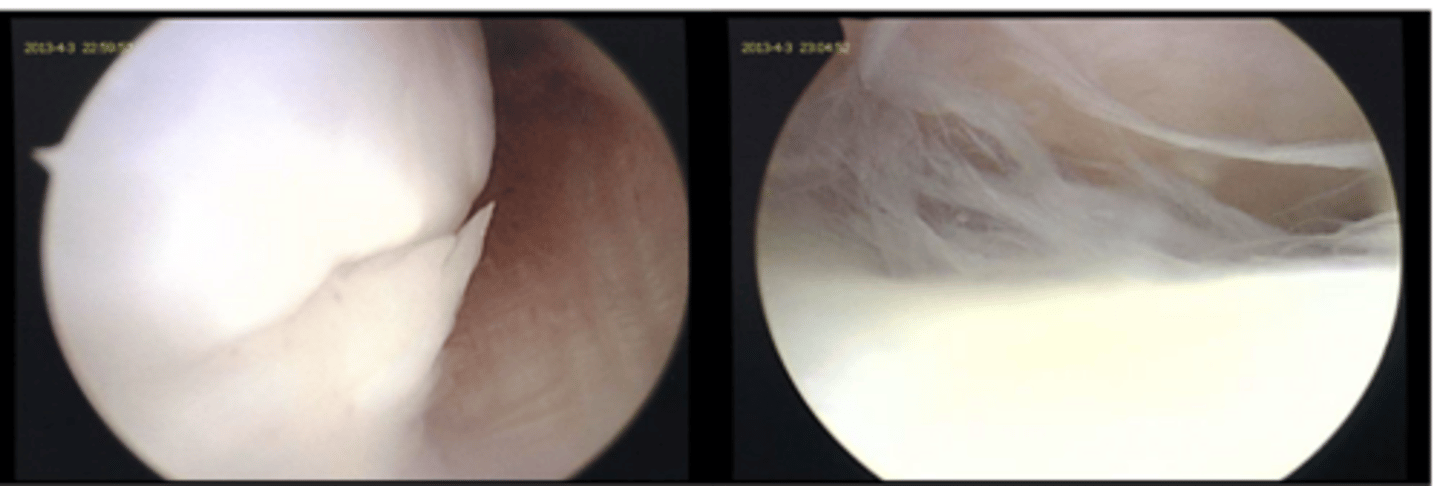

what damage is notable in this deranged stifle joint

1. cranial and caudal cruciate ligament tears

2. failure of primary and secondary medial restraints

3. peripheral medial meniscal tears

what is the common triad of multiple ligament injuries

deranged stifle...multiple lig. injuries often associated w/ meniscal injury and stifle luxation

what condition is shown here